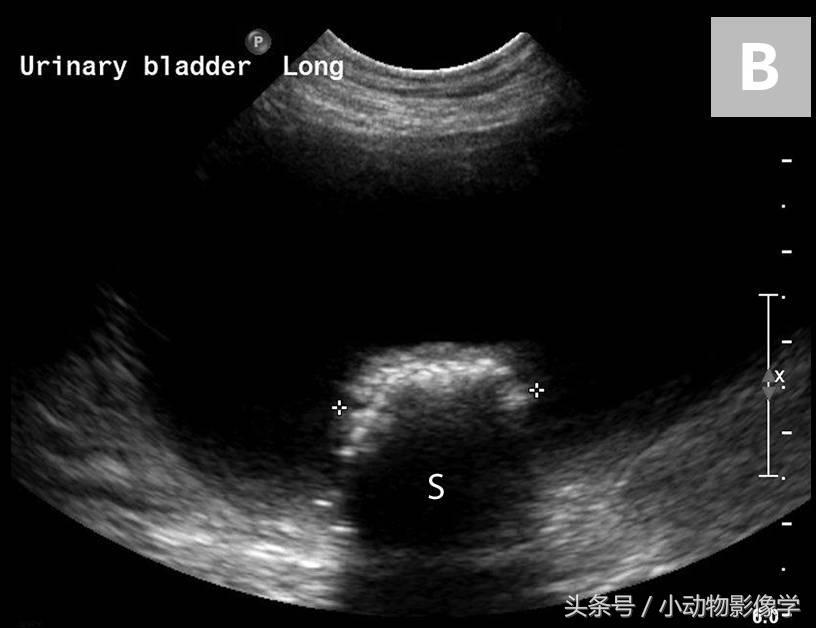

图8B、图8A中犬的超声图像。可见结石的不规则边缘及结石引起的远端声影伪像(S)。